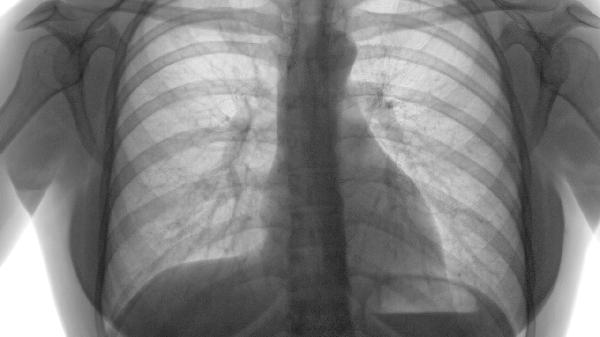

1、影像学特征:

胸部CT可显示肺气肿的典型表现,如肺组织透亮度增高、肺血管纹理稀疏、胸膜下肺大疱等。但早期肺气肿或轻度病变可能仅表现为局部透亮度轻微改变,单次CT扫描可能无法捕捉到明确征象。动态随访CT对比或高分辨率CT能提高检出率。